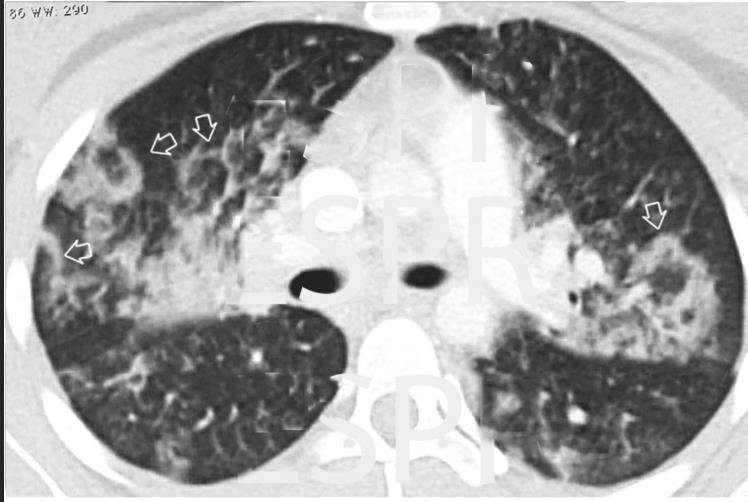

Acute Pediatric COVID-19: CT

21 Imaging of Covid 19 infection in children

3 Phases

Early: "Halo" sign

Local infection

Progressive: Diffuse GGO

Developed: Consolidation

Surr vasc congestion

Inflammation - adj alveoli

Alveoli fill with fluid/cells

• Bilateral & multifocal GGO, +/Consolidations or both

• Halo sign

• Peripheral and subpleural

• Bronchovascular thickening